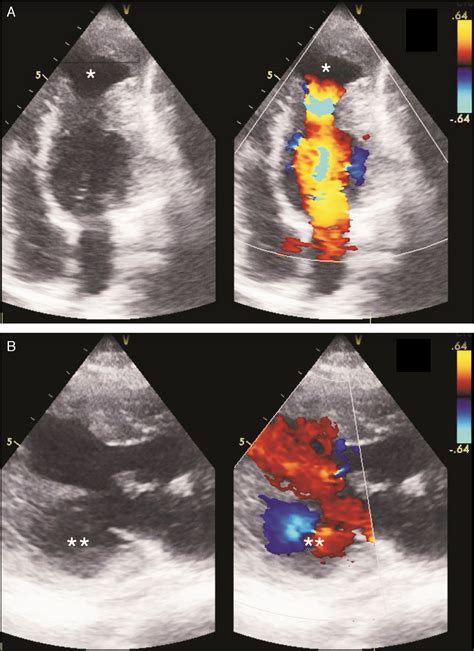

• Echocardiogram: This uses sound waves to create images of the heart, allowing doctors to visualize the aneurysm and assess its size and location.

• left ventricular aneurysm vs pseudoaneurysm